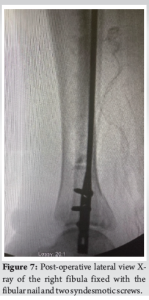

The patient underwent a comprehensive orthopedic surgical procedure to address a complex right ankle injury, specifically a trimalleolar equivalent ankle fracture with syndesmotic rupture. The procedure included ORIF of the fibula using the Fibulock Intramedullary (IM) Fixation system, butterfly fragment fixation utilizing FiberTape, and syndesmotic repair. The surgical approach involved anesthetic management with a laryngeal mask airway and a pre-operative popliteal block administered to the right lower extremity. The patient’s right lower extremity and foot were meticulously scrubbed, prepped, and draped using a standard aseptic technique. Fluoroscopy was employed throughout the procedure to confirm anatomical alignment, and the surgical site was thoroughly irrigated with normal saline. The procedure began with a 3 cm incision on the lateral aspect of the distal fibula, proximal to the fracture site. Using a combination of blunt and sharp dissection, the hematoma was irrigated with normal saline, and the fracture site was localized under fluoroscopy. Coagulated blood was removed, soft-tissue impingements were addressed, and a reduction clamp was applied to reapproximate the bone fragments. To further stabilize the fracture, an angled hemostat was used to place FiberTape around the fibula fracture, encircling the fibular shaft at the butterfly fragment. The cerclage suture tails were secured to provide tension to the FiberTape, and fragment apposition was confirmed under fluoroscopy. Next, attention was directed to the lateral aspect of the right ankle, where a longitudinal incision was made 1 cm distal to the fibula’s tip. Percutaneous reduction of the fibular fracture was achieved with appropriate alignment of the ankle joint and fracture reduction. A guidewire was advanced from the distal aspect of the fibula through the fracture site, followed by drilling the fibula with an IM drill. The diaphyseal canal was reamed, and a 3 × 130 mm fibular nail, assembled with a target guide, was inserted through the incision. The fibular nail facilitated the reduction of the ankle fracture, and two syndesmotic screws were applied within the fibular construct to enhance ankle stability and provide additional support to the posterior malleolus fragment (Fig. 6 and 7).

The patient tolerated the procedure well and was transferred from the operating room to the recovery area with stable vital signs and intact neurovascular status (Fig. 8-10).